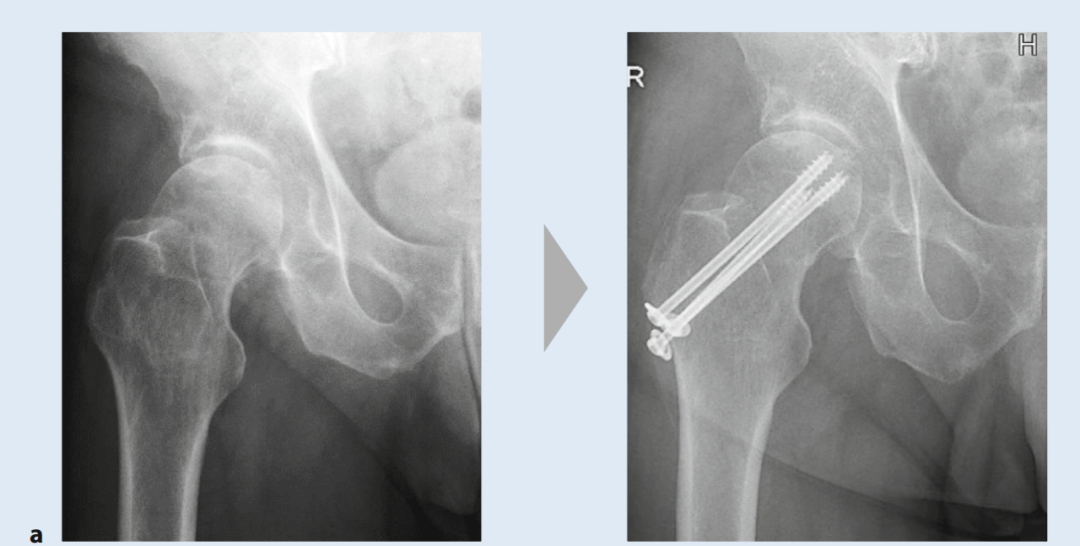

对于无移位股骨颈骨折,由于存在继发性移位风险以及需要数周制动,通常也建议手术治疗(图4)。根据一项荟萃分析的结果,绝大多数无移位骨折患者也能从手术稳定中获益。接骨术后的骨性愈合率为92.6%,而保守治疗下只有68.8%的骨折能够愈合。手术治疗的坏死发生率也较低(7.7% vs. 10.3%)。麻醉方式的选择(全身麻醉 vs. 区域麻醉)似乎对术后结果没有影响。

图4. 股骨颈骨折术前术后X光片(治疗方式对比):a) 螺钉内固定术,b) 双动头置换术,c) 全髋关节置换术